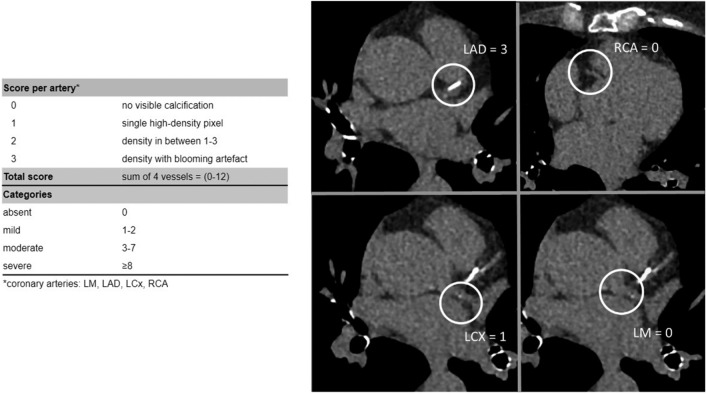

To enhance risk stratification in patients suspected of coronary artery disease, the assessment of coronary artery calcium (CAC) could be incorporated, especially when CAC can be readily assessed on previously performed non-gated chest computed tomography (CT). Guidelines recommend reporting on patients' extent of CAC on these non-cardiac directed exams and various studies have shown the diagnostic and prognostic value. However, this method is still little applied, and no current consensus exists in clinical practice. This review aims to point out the clinical utility of different kinds of CAC assessment on non-gated CTs. It demonstrates that these scans indeed represent a merely untapped and underestimated resource for risk stratification in patients with stable chest pain or an increased risk of cardiovascular events. To our knowledge, this is the first review to describe the clinical utility of different kinds of visual CAC evaluation on non-gated unenhanced chest CT. Various methods of CAC assessment on non-gated CT are discussed and compared in terms of diagnostic and prognostic value. Furthermore, the application of these non-gated CT scans in the general practice of cardiology is discussed. The clinical utility of coronary calcium assessed on non-gated chest CT, according to the current literature, is evident. This resource of information for cardiac risk stratification needs no specific requirements for scan protocol, and is radiation-free and cost-free. However, some gaps in research remain. In conclusion, the integration of CAC on non-gated chest CT in general cardiology should be promoted and research on this method should be encouraged.